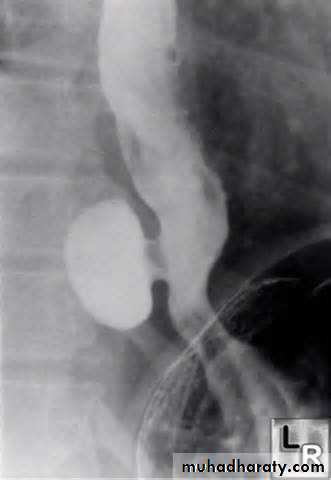

Hiatal Hernia

Sliding (L) & rolling (R) hiatal hernias

Hiatal hernias